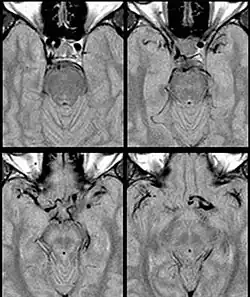

Internal carotid artery dolichoectasia is particularly interesting because the artery normally already contains one hairpin turn. Seen in an MRI as two individual arteries at this hairpin, a carotid artery dolichoectasia can progress so far as to produce a second hairpin turn and appear as three individual arteries on an MRI. In the case of a dolichoectasia of the Internal Carotid Artery (ICD), the pathogenesis is primarily related to compression of the optic nerves at the optic chiasma (see Fig. 1 and 2).